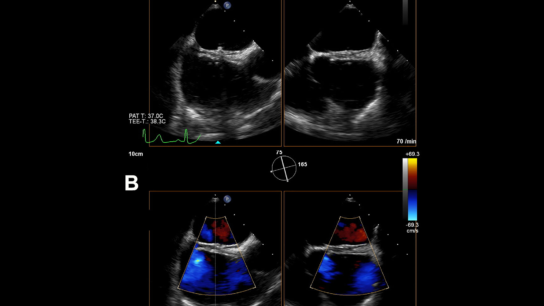

Patients with AF with a high bleeding risk and a low stroke risk may benefit from LAAO over oral anticoagulation.

Atrial fibrillation, which affects up to 46.3 million people globally and 2.7 to 6.1 million individuals in the US, may represent a modifiable risk factor for acute stroke.